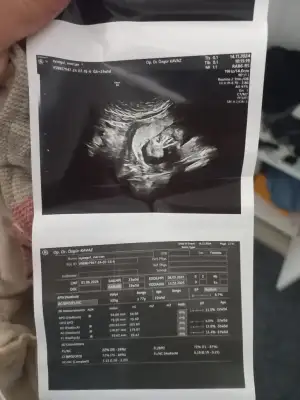

Canım, öncelikle çok geçmiş olsun. Neler yaşadın bilmiyorum, stres yapma demek çok kolay. 1 ay önce dedem vefat etti ve kendimi tıtamadan sürekli ağlıyordum. Psikoloğumla konuştuğumda annelik içgüdüsü baskın geliyor genelde akışına bırakın dedi ama ne kadar sürerdi bilmiyorum. Şöyle anlatayım “maske” taktım. Yasımı erteledim ve en fazla 3 gün ağladım. Uzaktayım, dedemle vedalaşamadım bile. Belki uzakta olmam benim hayrıma işledi. Belki annelik içgüdüm daha baskındı. Şurada toplam 9 ay herşeyi kenara bırakarak sadece bebeğimizi düşünme zamanı. Gün boyunca sadece meditasyon, rahatlama egzersizi ve yoga yapıyorum. Bir de kaynanamla yaşadığım için fırsat buldukça yılan gibi sokuyor. Hamile kalmadan önce ve ilk aylarında alttan almayıp tartışır ve geceleri uyuyamadığım anlar olurdu. Ultrasonda ileri derecede rahim kasılmamı görünce kendime çok kızdım. İnan değmez, şuan hiçbir şey minnacık yavrularımızdan daha önemli değil. İmkanın varsa stres yaşatan şeyleri ertele, yoksay ve yoga yap. Stresin en büyük etki aracı da nefesimiz. Bol bol nefes almaya ve rahatlamaya çalış stresin gitgide azalacaktır.